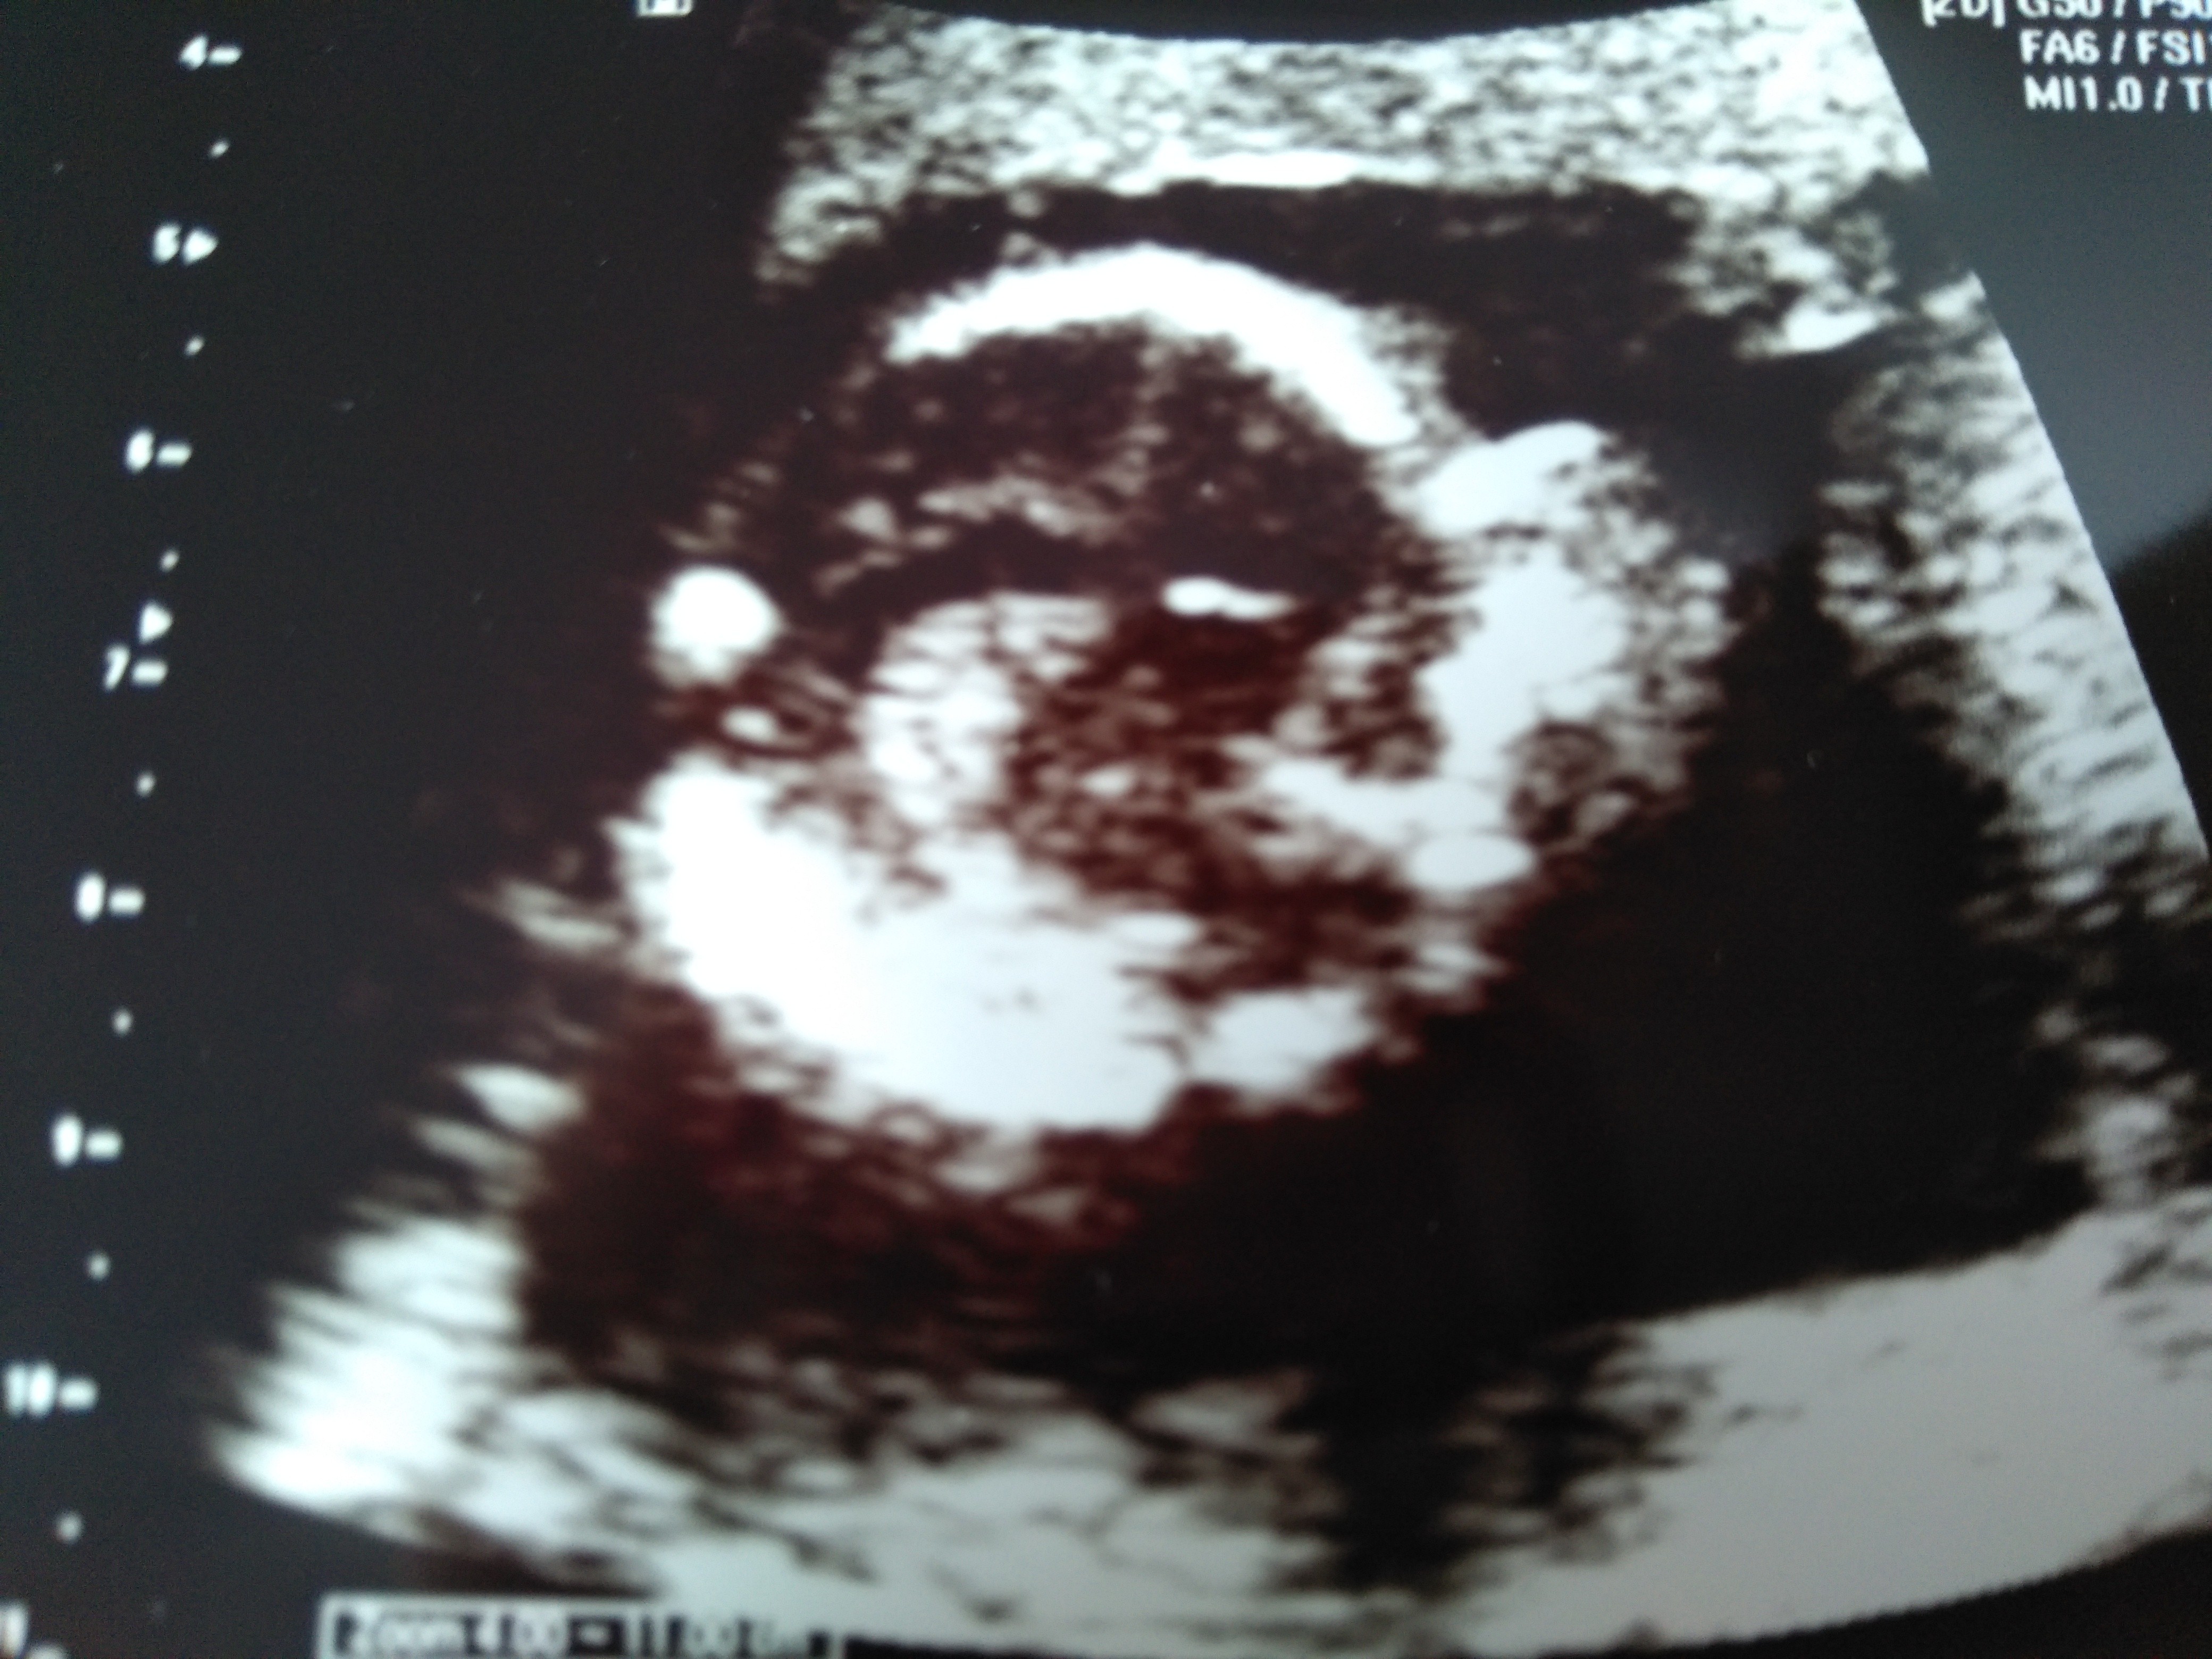

właśnie wróciłam u dzidzi wszystko ok waży już 168g serduszko bije pięknie 159 zaraz spróbuję zdjęcie wrzucić :) dostałam tylko jedno bo się skarbuś tak ruszał, że trudno było ładne zrobić całego :) na połówkowych będzie więcej czasu to może lepiej zobaczymy... płci nadal nie pokazał uparciuszek :p

Oto mój Skarbuś

• IMG_20180825_133745.jpg

1,8 MB · Wyświetleń: 88